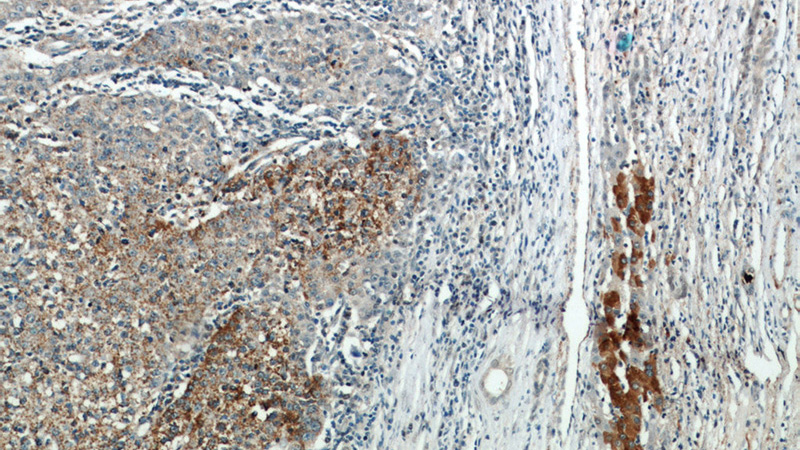

Immunohistochemical of paraffin-embedded human liver cancer using Catalog No:113872(PIK3CB antibody) at dilution of 1:50 (under 10x lens)